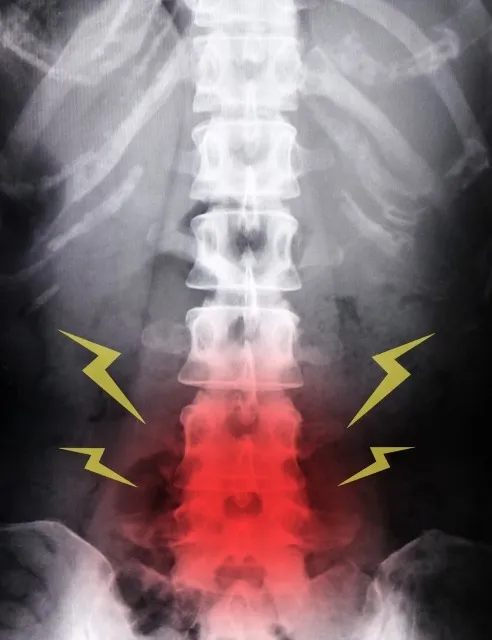

腰椎椎間板ヘルニアの原因と整体施術解説 2025/11/07 腰椎椎間板ヘルニアは、多くの人が経験する腰痛の代表的な原因のひとつです。椎間板が何らかの原因で変性し、内部の髄核が飛び出すことで神経を圧迫し、腰痛やしびれ、脚の痛みなどの症状を引き起こしま…

背骨の歪みを整えて痛みを改善する整体技術 2025/10/18 背骨の歪みは身体のさまざまな痛みや不調の原因となることが多く、整体院ではその調整技術が重要視されています。背骨は体の中心を支える大切な部分であり、その状態が悪くなると神経の圧迫や筋肉のバラ…